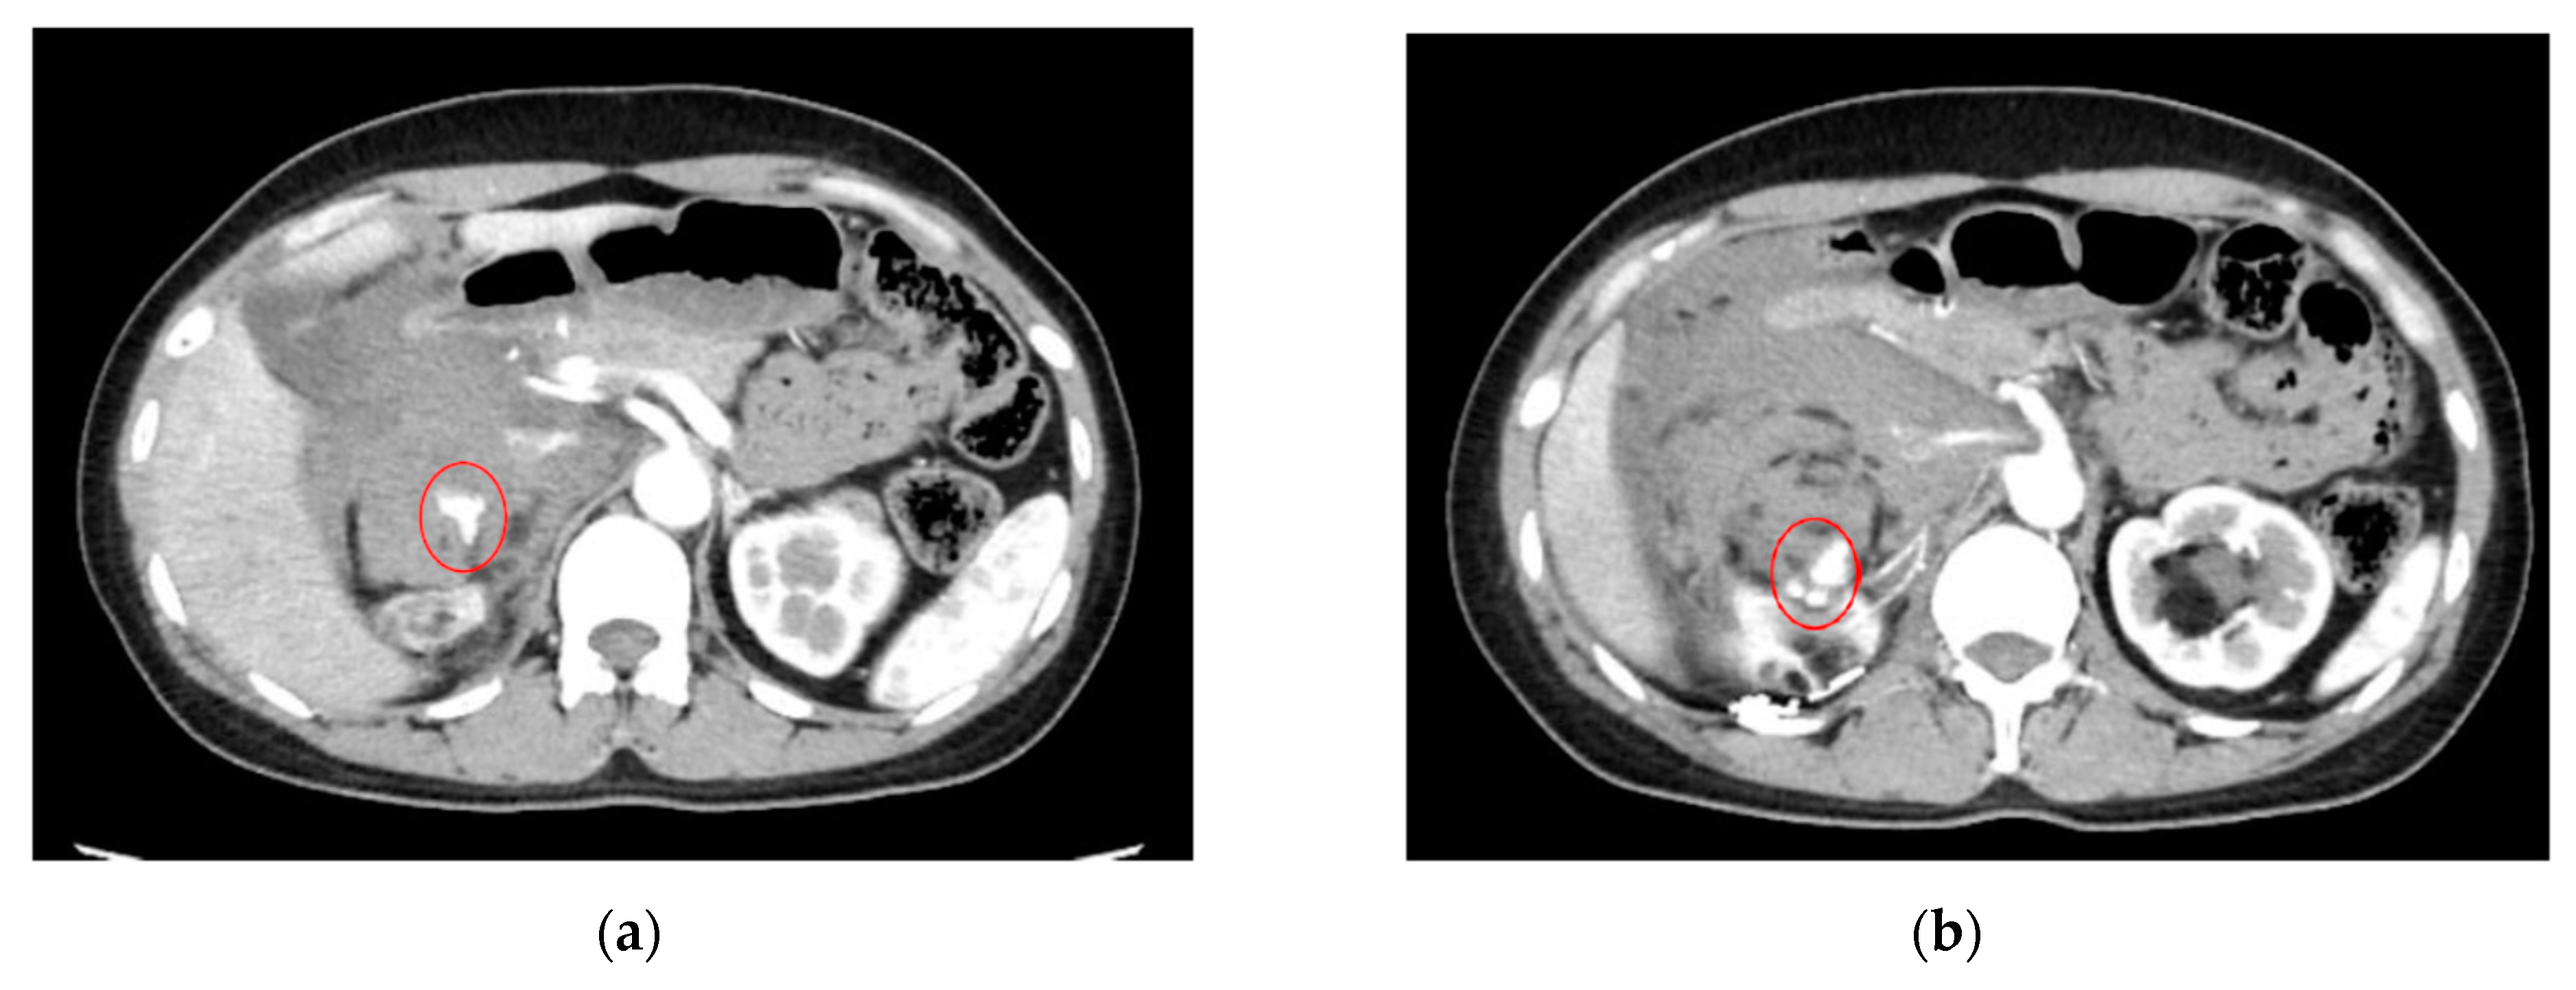

As an illustration, Figure 4 depicts an extravasation-induced hemorrhage from kidney angiomyolipoma, a condition characterized by the formation of benign tumors in the kidney. Patients with this condition may experience a range of symptoms, including anemia, fever, pain, or high blood pressure. In cases where tumors grow, treatment such as embolization or surgery may be necessary to mitigate the risk of bleeding.

Figure 4.

Extravasation-indued hemorrhage from kidney angiomyolipoma for both (a,b) shown with circles.

Figure 5 illustrates an extravasation-induced hemorrhage resulting from the rupture of hepatocellular carcinoma in a 68-year-old male patient. This individual had previously undergone transcatheter arterial chemoembolization, a minimally invasive and targeted treatment utilized for managing certain advanced liver tumors that are not amenable to surgical removal. Following the rupture, the patient was admitted to the hospital in a state of hypotension, characterized by low blood pressure. This case underscores the importance of closely monitoring patients with hepatocellular carcinoma, particularly those who have undergone chemoembolization, for potential complications such as extravasation.

Figure 5.

Extravasation-induced hemorrhage marked with a circle due to the rupture of hepatocellular carcinoma.

Additionally, Figure 6 delineates the locations of extravasation detected in a patient’s lung cancer as visualized on CT images. Specifically, in panel (b), one of the feeding arteries of the tumor (the right bronchial arterial) is depicted. Identifying the responsible vessel on CT proved challenging, leading to the decision to embolize this artery. The patient had previously experienced hemoptysis prior to initiating chemotherapy.

Figure 6.

Lung cancer extravasation sites highlighted with circles in (a,b).